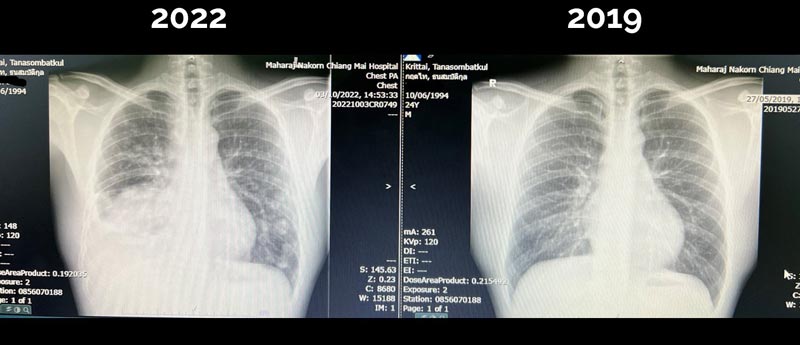

จากกรณีเรื่องราวสะเทือนใจที่ถูกแชร์ต่อบนโลกออนไลน์ในขณะนี้ กับโพสต์จากเพจ "สู้ดิวะ" ของ คุณหมอกฤตไท ธนสมบัติกุล แพทย์หนุ่มอนาคตไกล วัย 28 ปี ที่เพิ่งพบว่าตัวเองป่วยเป็นมะเร็งปอดระยะสุดท้าย แม้ดูแลร่างกายตัวเองเป็นอย่างดี ชีวิตที่กำลังเดินไปข้างหน้ากลับต้องพลิกผัน